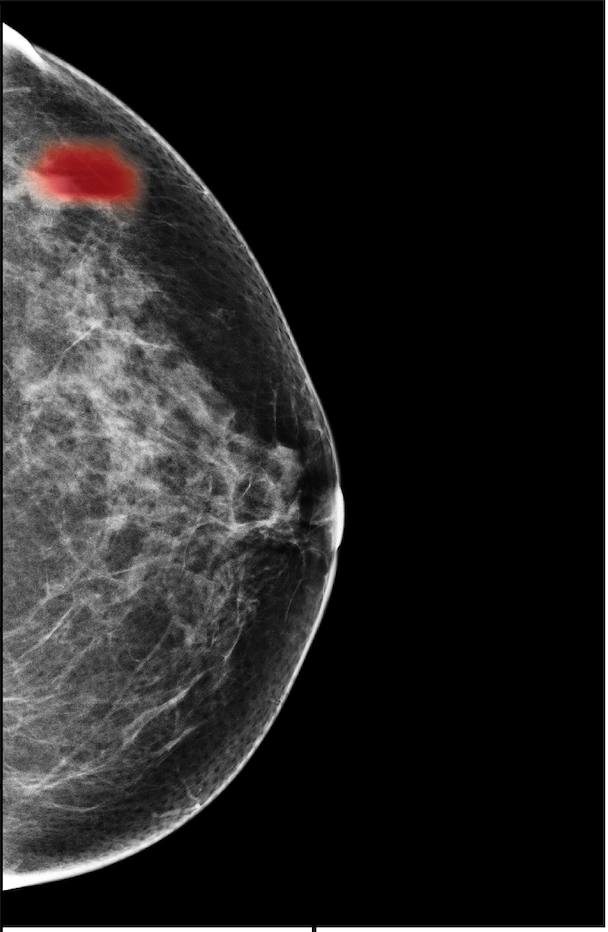

In Figure 7, we visualize saliency maps for four samples selected from the test set. In the first two examples, the saliency maps are highly activated on the annotated lesions, suggesting that our model is able to detect suspicious lesions without pixel-level supervision. Moreover, the attention is highly concentrated on ROI patches that overlap with the annotated lesions. In the third example, the saliency map for benign findings identifies three abnormalities. Although only the top abnormality was escalated for biopsy and hence annotated by radiologists, the radiologist’s report confirms that the two non-biopsied findings have a high probability of benignity and a low probability of malignancy. In the fourth example, we illustrate a case when there is some level of disagreement between our model and the annotation in the dataset. The malignancy saliency map only highlights part of a large malignant lesion with segmental coarse heterogeneous calcifications. This behavior is related to the design of : a fixed pooling threshold cannot be optimal for all sizes of ROI. The impact of is further studied in 3.6. This example also illustrates that while human experts are asked to annotate the entire lesion, CNNs tend to emphasize only the most informative regions. While no benign lesion is present, the benign saliency map still highlights regions similar to that in the malignancy saliency map, but with a lower probability than the malignancy saliency map. In fact, calcifications with this morphology and distribution can also result from benign pathophysiology [42].

The NYU Breast Cancer Screening Dataset [78] includes 229,426 exams (1,001,093 images) from 141,472 patients.222Our retrospective study was approved by our institutional review board and was compliant with the Health Insurance Portability and Accountability Act. Informed consent was waived. Each exam contains at least four images which correspond to the four standard views used in screening mammography: R-CC (right craniocaudal), L-CC (left craniocaudal), R-MLO (right mediolateral oblique) and L-MLO (left mediolateral oblique). An example is shown in Figure 3.

For all exams matched with biopsies, we asked a group of radiologists (provided with the corresponding pathology reports) to retrospectively indicate the location of the biopsied lesions. This way we obtained the segmentation labels: where if pixel belongs to the benign/malignant findings. An example of such a segmentation is shown in Figure 3. In all experiments (except for experiments in Section 3.6 that assess the benefits of utilizing segmentation labels), segmentation labels are only used for evaluation. We found that, according to the radiologists, approximately of exams were mammographically occult, i.e., the lesions that were biopsied were not visible on mammography, even retrospectively, and were identified using other imaging modalities: ultrasound or MRI.